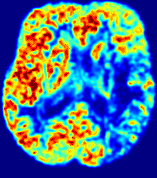

LesionRefer to captionRefer to captionRefer to captionRefer to captionRefer to captionRefer to caption𝐕rgbsubscript𝐕𝑟𝑔𝑏{\bf{V}}_{rgb}Refer to captionRefer to captionRefer to captionRefer to captionRefer to captionRefer to caption𝐕2subscriptnorm𝐕2{\|\bf{V}}\|_{2}Refer to captionRefer to captionRefer to captionRefer to captionRefer to captionRefer to captionRefer to caption3.53.53.52.82.82.82.12.12.11.41.41.40.70.70.70.00.00.0(mm/s)𝑚𝑚𝑠(mm/s)D𝐷DRefer to captionRefer to captionRefer to captionRefer to captionRefer to captionRefer to captionRefer to caption0.0200.0200.0200.0160.0160.0160.0120.0120.0120.0080.0080.0080.0040.0040.0040.0000.0000.000(mm2/s)𝑚superscript𝑚2𝑠(mm^{2}/s)Slice #1Slice #2Slice #3Slice #4Slice #5Slice #6

Figure 4: PIANO feature maps for another patient in the ISLES 2017 training set, where the lesion is located in the right hemisphere. Top row: segmented stroke lesion region (white) on different slices. The corresponding slices for the PIANO feature maps are shown in the following rows.

For a better insight into an estimated velocity field 𝐕𝐕{\bf{V}} and diffusion field 𝐃𝐃{\bf{D}}, we compute the following maps: (1) 𝐕rgbsubscript𝐕𝑟𝑔𝑏{\bf{V}}_{rgb}: Color-coded orientation map of 𝐕=(Vx,Vy,Vz)T𝐕superscriptsuperscript𝑉𝑥superscript𝑉𝑦superscript𝑉𝑧𝑇{\bf{V}}=(V^{x},V^{y},V^{z})^{T}, obtained by normalizing 𝐕𝐕{\bf{V}} to unit length and mapping its 3 components to red, green, blue respectively; (2) 𝐕2subscriptnorm𝐕2\|{\bf{V}}\|_{2}: 222 norm of 𝐕𝐕{\bf{V}}; (3) D𝐷D: scalar field in Eq. 5.

Fig. 3 and Fig. 4 show the PIANO feature maps estimated from two ISLES 2017 patients: all are highly consistent with the lesion in both cases. Details of the blood flow trajectories are revealed in 𝐕rgbsubscript𝐕𝑟𝑔𝑏{\bf{V}}_{rgb} by the ridged patterns and the sharp changes of colors in the unaffected (right) hemisphere, while the flat patterns appearing within the lesion provide little directional information about the velocity and indicate low velocity magnitudes. Velocity magnitudes are more directly visualized via 𝐕2subscriptnorm𝐕2\|{\bf{V}}\|_{2}, from which one can easily locate the lesion where 𝐕2subscriptnorm𝐕2\|{\bf{V}}\|_{2} is low. D𝐷D also indicates lower diffusion values in the lesion, though with less contrast potentially due to the fact that it captures the accumulated effect of CA diffusion at the voxel-level.